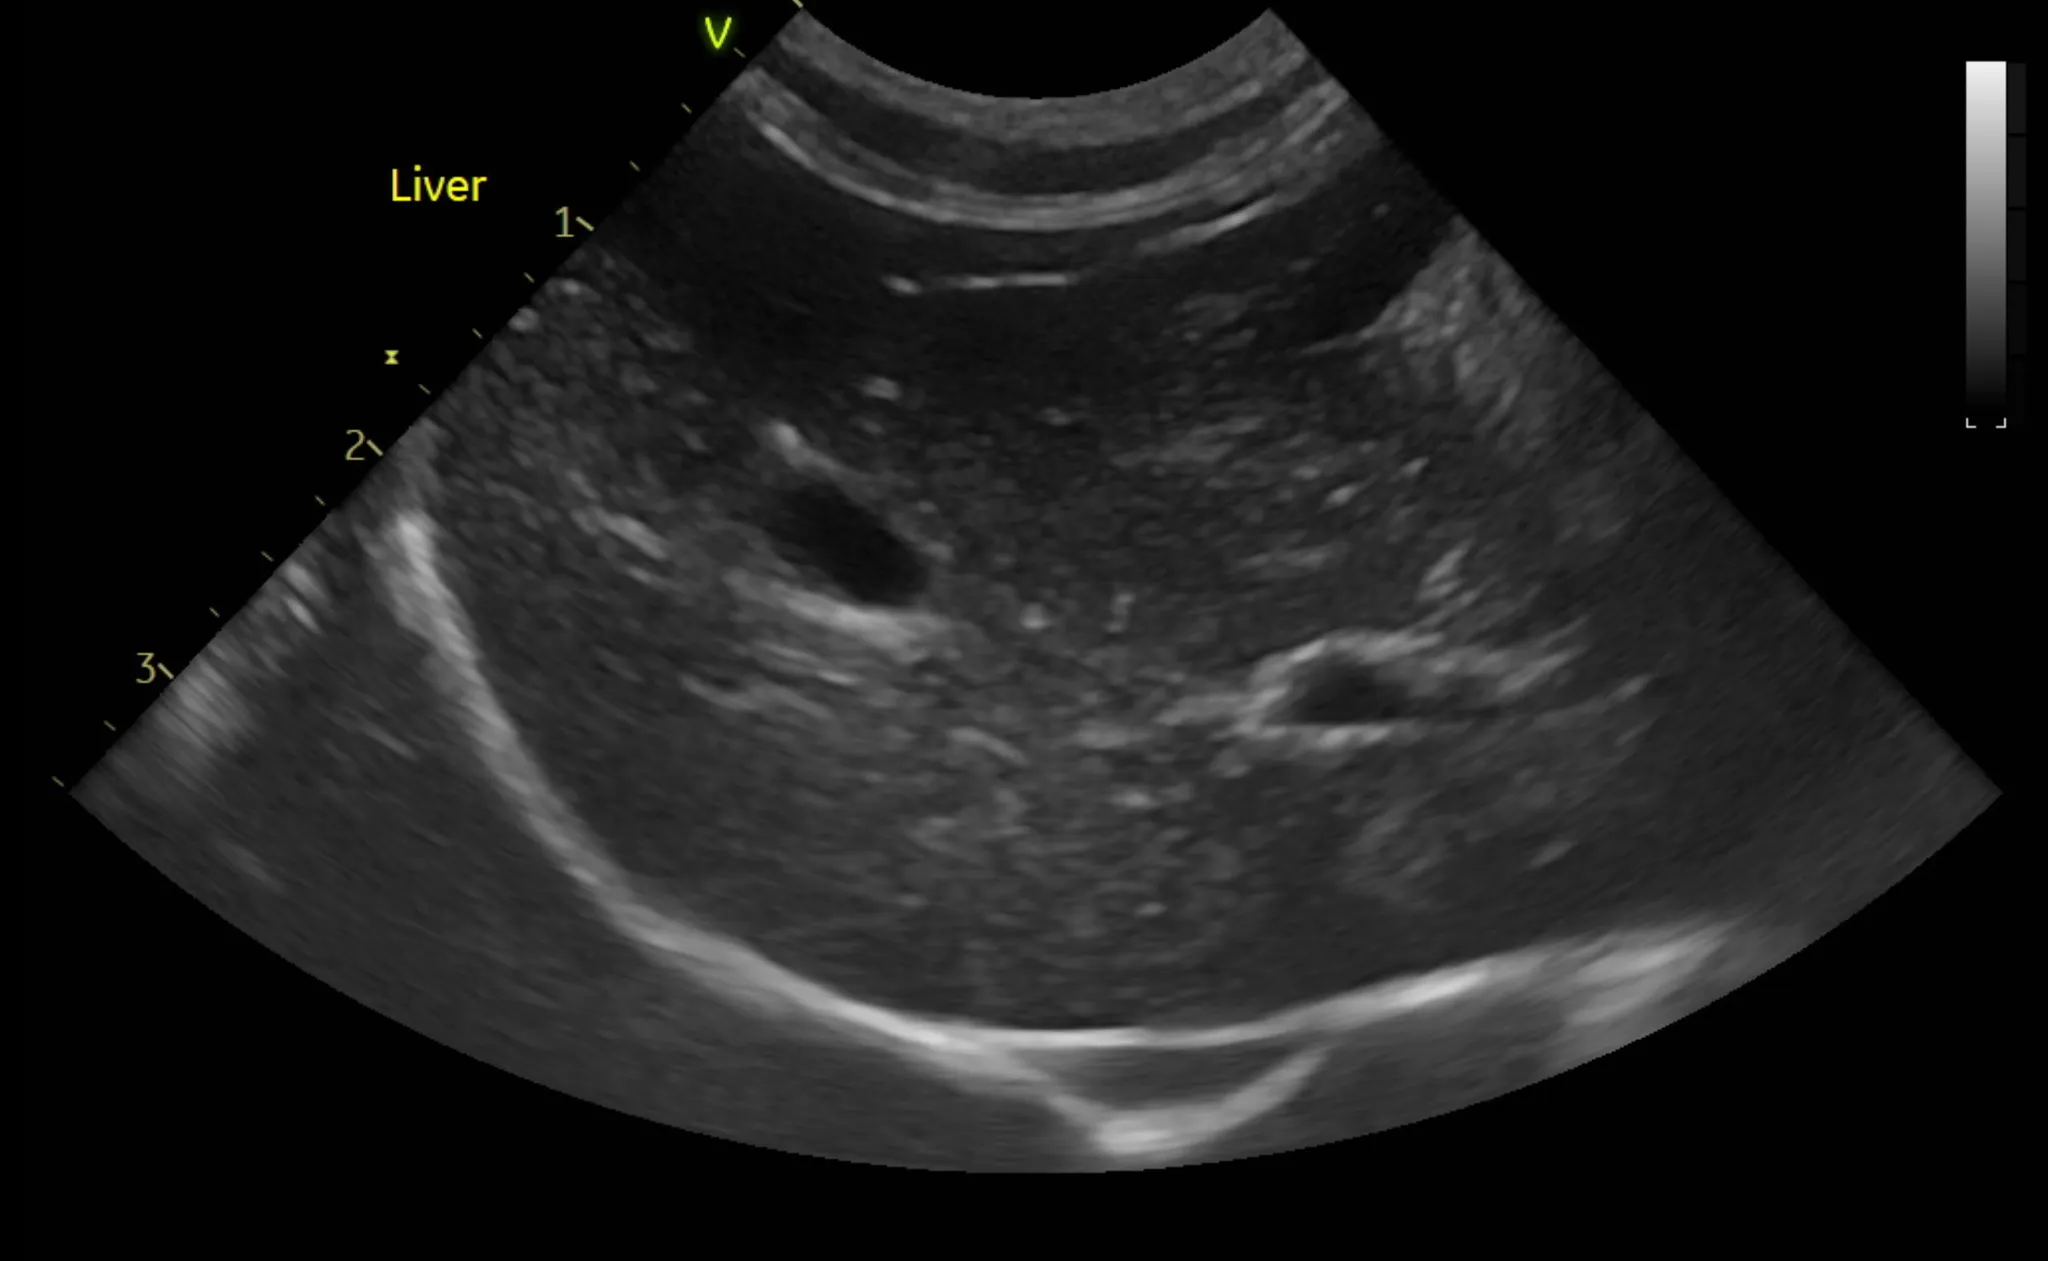

3. 복부 초음파 검사 결과

복부 초음파 검사로는 간, 신장 등 복부 장기의 모양과 결석, 종양등의 이상여부를 알 수 있습니다.

또한 방광 결석, 다낭포성 신장질환 같은 고양이에서 잘 생기는 질환의 경우 초음파 검사로만 알 수 있으므로 매우 중요한 검사 중 하나입니다.

복부 초음파 검사 상 특이사항은 발견되지 않았습니다.

1년 주기로 검사를 추천드립니다.